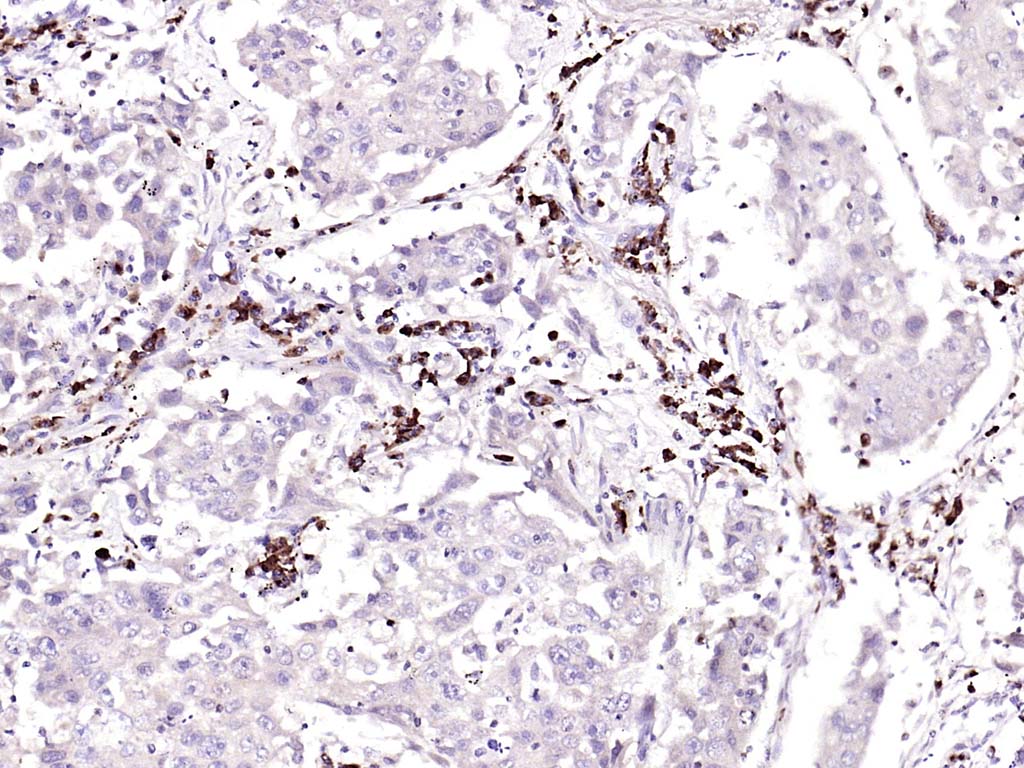

Paraformaldehyde-fixed, paraffin embedded (mouse adrenal gland); Antigen retrieval by boiling in sodium citrate buffer (pH6.0) for 15min; Block endogenous peroxidase by 3% hydrogen peroxide for 20 minutes; Blocking buffer (normal goat serum) at 37°C for 30min; Antibody incubation with (GSTA3) Polyclonal Antibody, Unconjugated (bs-5163R) at 1:200 overnight at 4°C, followed by operating according to SP Kit(Rabbit) (sp-0023) instructionsand DAB staining.

Paraformaldehyde-fixed, paraffin embedded (human lung carcinoma); Antigen retrieval by boiling in sodium citrate buffer (pH6.0) for 15min; Block endogenous peroxidase by 3% hydrogen peroxide for 20 minutes; Blocking buffer (normal goat serum) at 37°C for 30min; Antibody incubation with (GSTA3) Polyclonal Antibody, Unconjugated (bs-5163R) at 1:200 overnight at 4°C, followed by operating according to SP Kit(Rabbit) (sp-0023) instructionsand DAB staining.

Tissue/cell: rat brain tissue; 4% Paraformaldehyde-fixed and paraffin-embedded; Antigen retrieval: citrate buffer ( 0.01M, pH 6.0 ), Boiling bathing for 15min; Block endogenous peroxidase by 3% Hydrogen peroxide for 30min; Blocking buffer (normal goat serum,C-0005) at 37℃ for 20 min; Incubation: Anti-GSTA3 Polyclonal Antibody, Unconjugated(bs-5163R) 1:200, overnight at 4°C, followed by conjugation to the secondary antibody(SP-0023) and DAB(C-0010) staining